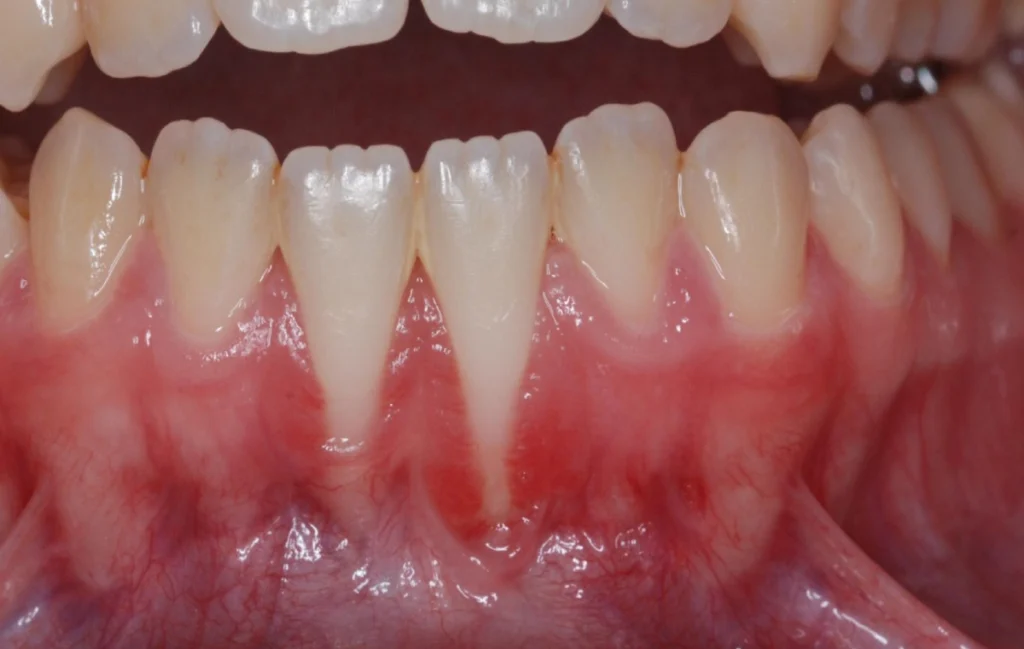

La récession gingivale

La récession gingivale est l’une des principales indications. Elle survient lorsque les gencives se rétractent, exposant les racines des dents. Cela peut être dû à un brossage agressif, à une maladie parodontale ou à un traumatisme. La chirurgie muco-gingivale couvre les racines exposées et renforce les gencives.